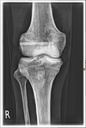

Dieses weltweit einmalige Phantom bietet erstklassige Übungsmöglichkeiten für die Lagerungs- und Einstelltechnik in der Projektions-Radiographie und gehört eigentlich zur Grundausstattung jeder Röntgen-Ausbildungsstätte. Das Phantom enthält ein natürliches menschliches Skelett sowie die Umrisse von Kehlkopf, Lunge, Herz und Nieren (Organe erscheinen als Schatten auf den Röntgenbildern), dadurch können mit dem Phantom echte Röntgenaufnahmen wie beim Patienten gemacht werden. Durch die Verwendung des echten Skeletts können Leitstrukturen im Knochen erkannt werden, was bei Kunststoffskeletten nicht möglich ist. Bei der Montage des Phantoms wird besonderer Wert auf die Darstellung der Gelenkspalte gelegt. Die Gelenke sind voll beweglich montiert, und ermöglichen die Lagerung in den normalen Röntgenpositionen (z.B. Froschposition, Pro- und Supination des Unterarms). Die Arme können nach oben bewegt werden, so dass das Modell auch für alle knöchernen Untersuchungen im CT verwendet werden kann. Bei jedem Phantom handelt es sich um ein handgefertigtes Unikat, welches sich in Größe und Ausführung unterscheiden kann. Je nach Modell können pathologische Befunde vorhanden sein, die äußere Erscheinung kann sich je nach Größe des Modells unterscheiden. Die neue Ausführung dieses Modells wurde in Zusammenarbeit mit einer namhaften deutschen Schule für Med. Techn. Radiologieassistenten komplett überarbeitet und erfüllt alle Anforderungen für die Ausbildung. Der Verkauf dieses Phantoms erfolgt nur gegen Nachweis der medizinischen Verwendung. Natürliche Größe.